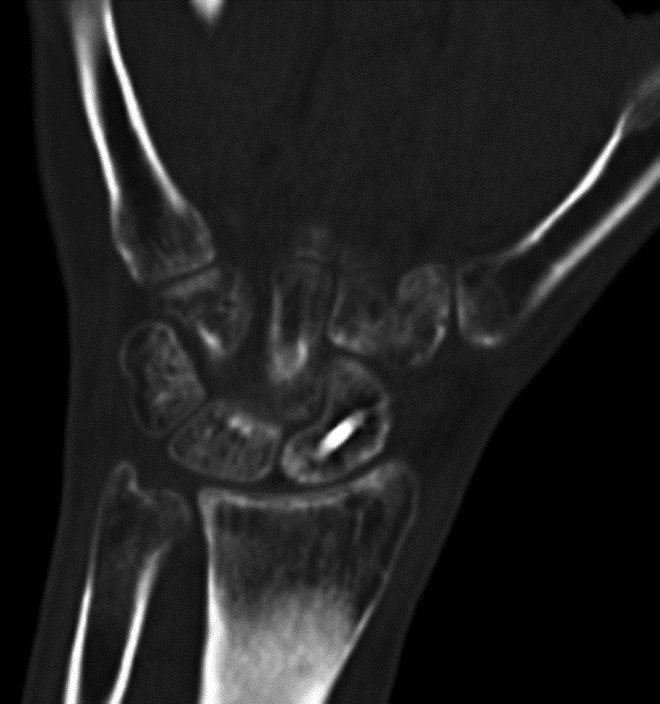

Scaphoid Fracture Evaluation. (A) Sagittal multiplanar reformation shows central portion of compression screw in the scaphoid with incomplete union at periphery of fracture site (arrowheads). Note absence of streak artifact due to small size of screw. (B) Coronal multiplanar reformation shows fracture union at the central portion of the scaphoid waist, indicating partial union.